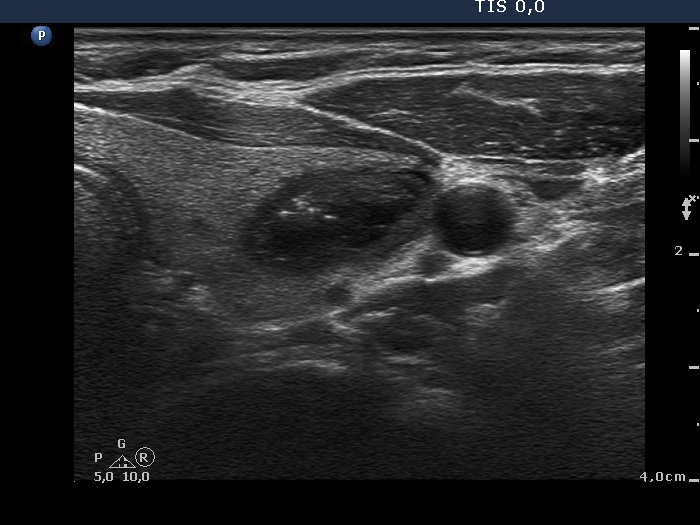

Ultrasonography. The thyroid was echonormal. There was a minimally-moderately hypoechogenic nodule in the right while a cystic nodule in the left lobe. There were numerous hyperechogenic figures both in the cystic and in the lower solid part of the lesion. The lesion presented no vascularization.

Comment. The presentation of the bright hyperechogenic granules are relatively unusual, they were mostly located within the solid part causing a false impression of starry sky phenomenon. In fact, they were comet-tail artifacts.